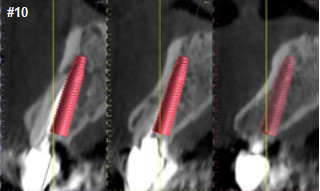

Upon prosthetic evaluation, since bothteeth were deemed unrestorable, the replacement plan an implant supported restoration. Radiographically, tooth #7 exhibited a moderate-sized periapical radiolucency.During the initial examination appointment, a CBCT and I-tero scans were obtained along with the appropriate shade to start planning an immediate non-functional tem-porary restoration. An intraoral scan was sent to the lab for digital planning of the temporary restorations.

A CBCT review showed adequate bone palatal to the socket wall, so the bone density appeared to be favorable for immediate implant placement.

Both sites were prepared into the solid palatal wall of the socket and the osteotomies were under prepared to achieve a minimum high insertion torque of at least 30N to be considered for non-functional immediately loaded temporization. 4.0x16mm implants were placed with an insertion torque above 50N at both sites. The jump gaps were grafted with cortical-cancellous allograft (Life-Net Salvin) in a dual zone fashion. The most coronal zone was packed with a moderate force to create more volume in the soft tissue compartment.

The implant must be planned and executed with a high precision as regards the position, angulation and depth in order to utilize the lab made custom temporary shells successfully.

The preferred depth of implant placement should be at least 3-4mm apical to the proposed facial gingival zenith (Linkevicius). An appropriate implant placement depth is crucial to provide adequate running room for the temporary and final restorations, a concave emergence with an adequate jump gap with the appropriate “regenerative space” (Gonzalez-martin) during dual zone grafting (Tarnow). In thin tissue phenotypes or in cases with pre-existing recession, soft tissue augmentation utilizing a connective tissue graft can be done at this time. Due to a favorable phenotype and the absence of any soft tissue defect, this case didn’t need a soft tissue graft.